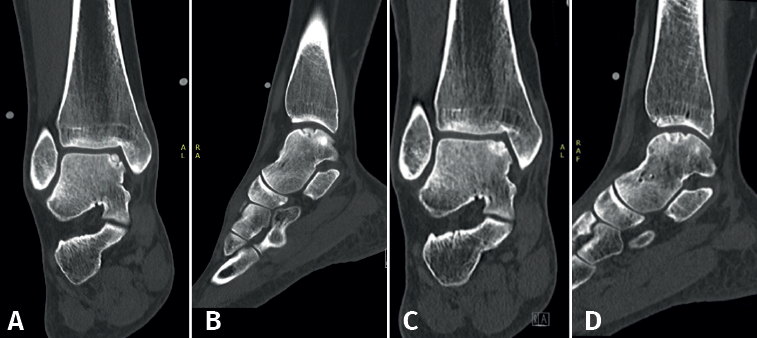

Lesions can be characterized by location, morphology, and size. Location can be described using a 9-grid anatomical scheme of the talus, as described by Raikin et al., shown in Figure 1(14). The morphology of OLTs can be described as crater-like, cystic, or fragmentary (Figure 2)(4,15,16). Lesion size should be reported in anterior-posterior plane, medial-lateral plane, and depth, allowing for calculation of lesion surface area and volume(4). However, there is no consensus on the reporting on morphology of OLTs, and while radiological classification systems for OLTs exist, they lack validation and utilize inconsistent terminology. Moreover, lesion size measurement methods vary, further contributing to inconsistency in lesion characterization in literature(15).